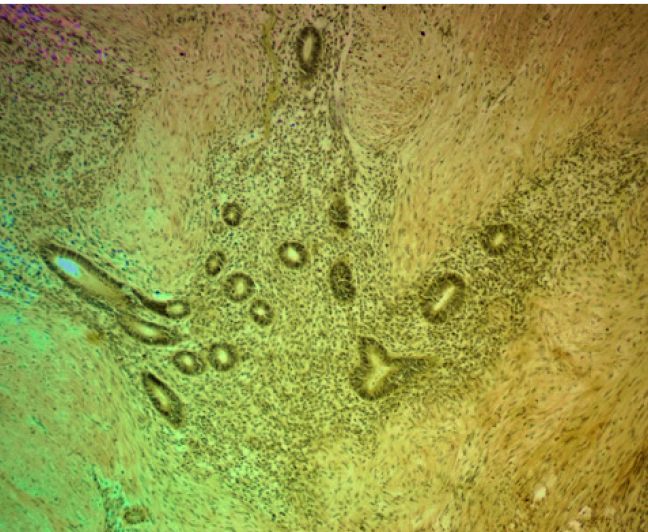

При гистологическом исследовании операционного материала во всех наблюдениях, независимо от органной локализации, патологический процесс характеризовался типовой для эндометриоза гистологической картиной: сочетанием желез, выстланных однорядным эпителием эндометриального типа с эндометриальной цитогенной стромой, вариабельной частотой кровоизлияний, отложением гемосидерина. Эндометриоидные гетеротопии имели преимущественно эпителиально-стромальное строение, очаги стромального эндометриоза встречались редко. В большинстве наблюдений эндометриоидные гетеротопии были множественными, размеры их варьировали от 1 до 2 полей зрения при луповом увеличении микроскопа. Эпителиальный и стромальный компоненты эндометриоидных гетеротопий характеризовались разнообразием морфофункциональных проявлений в виде пролиферации, секреции, кистозной трансформации желез с атрофией и/или десквамацией эпителия, подобно изменениям в эутопическом эндометрии в зависимости от фазы менструального цикла. Особенности и варианты морфофункциональных изменений в гетеротопиях зависели от органной локализации процесса. Для эндометриоза передней брюшной стенки характерной была выраженная тенденция к кистозной трансформации эндометриальных желез с атрофией и/или десквамацией эпителиальной выстилки. При поражении различных отделов кишечника в очагах эндометриоза обнаруживали преимущественно пролиферативные изменения в эпителиальном и стромальном компонентах гетеротопий. Независимо от органной локализации заболевания, в цитогенной строме очагов эндометриоза и в окружающих их тканях была обнаружена лимфо-макрофагальная инфильтрация различной степени выраженности, наибольшая − в местах отложения гемосидерина. В некоторых случаях выявлялась очаговая лимфо-макрофагальная инфильтрация по типу микроабсцессов. В таких инфильтратах встречались гигантские многоядерные клетки, присущие продуктивному воспалению и гранулемам инородных тел. Вокруг очагов эндометриоза и между ними было обнаружено разрастание «полей» соединительной ткани с большим количество коллагеновых волокон. Такая особенность в большей степени была присуща эндометриозу передней брюшной стенки, промежности и легкого (рис. 1, 2). При эндометриозе различных отделов кишечника площадь пролиферации соединительнотканных волокон вокруг гетеротопий была значительно меньше.

Рис. 1. Эндометриоз послеоперационного рубца. Окраска пикрофуксином по методу Ван-Гизон, ув. ×200

Рис. 2. Эндометриоз легкого. Окраска пикрофуксином по методу Ван-Гизон, ув. ×200